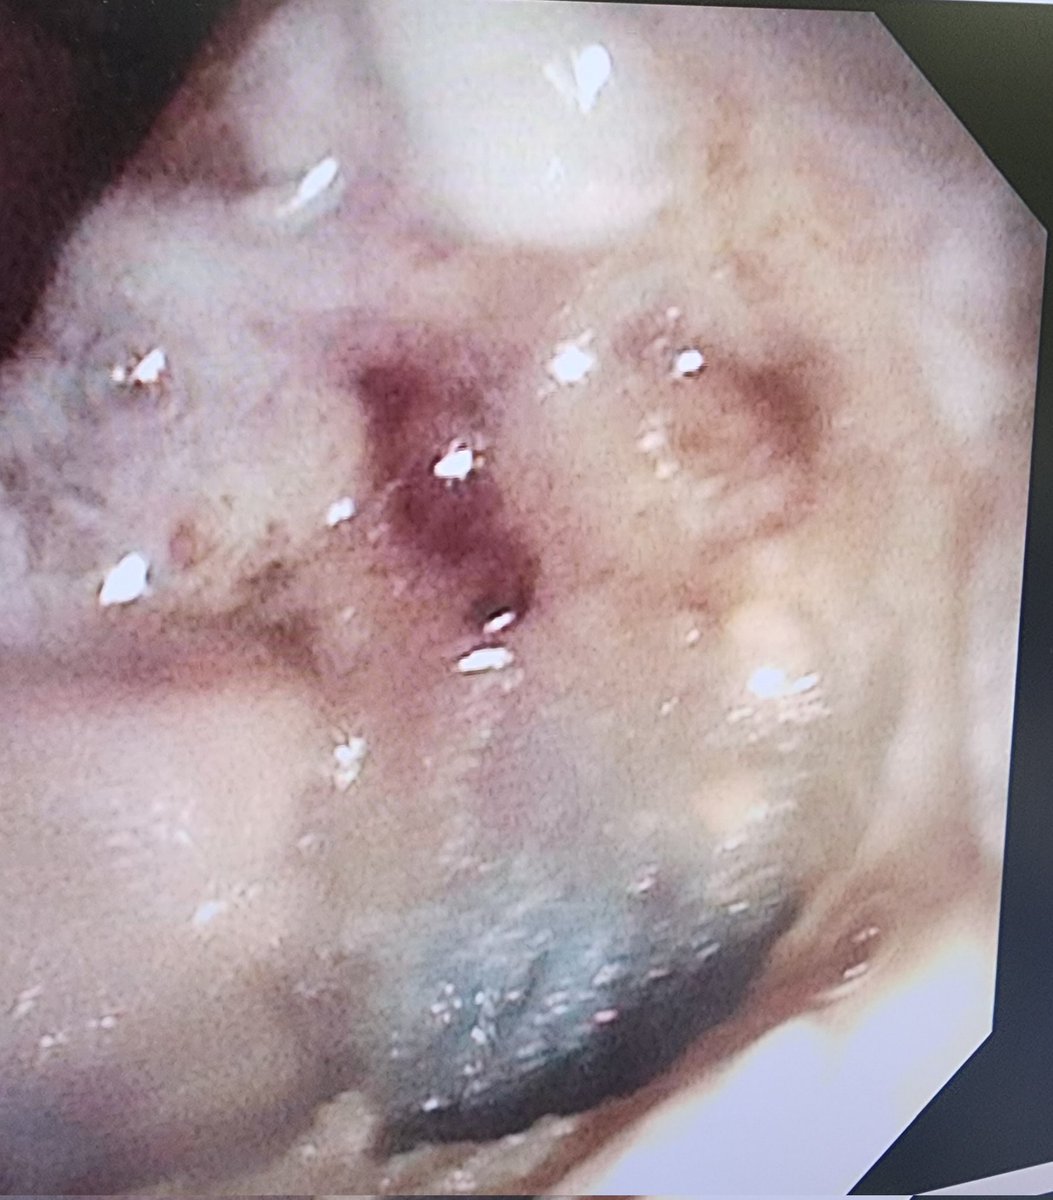

What’s this anechoic lesion?!!!!🤔